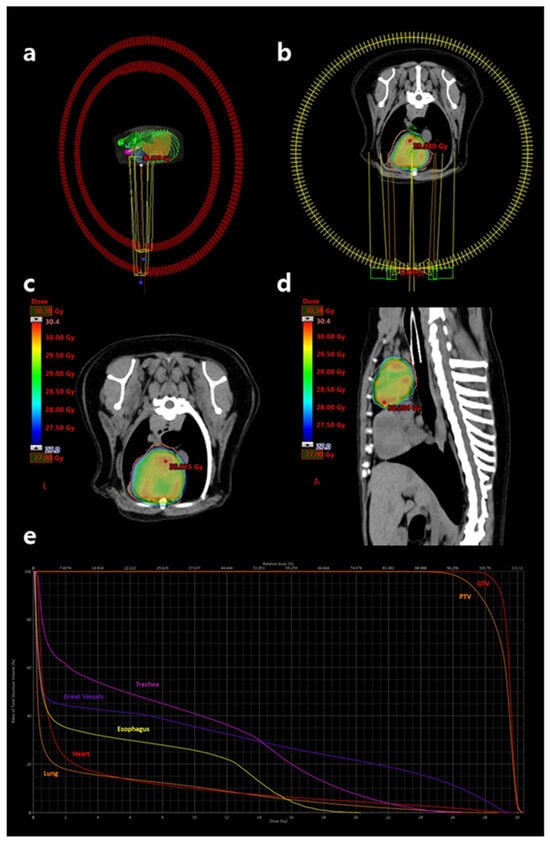

Figure 3. Radiation therapy planning performed using the Eclipse™ software version 13.7.33. (a,b) Schematic representations of the two coplanar 360-degree volumetric arcs used for stereotactic treatment. One arc rotates in a clockwise direction and the other in a counterclockwise direction. (c) Transverse and (d) sagittal views of the dose distribution over the cranial mediastinal mass. The dose color wash represents regions receiving doses equal to or greater than prescribed dose of 27 Gy, with the red dot indicating the maximum dose hotspot on the corresponding slice. (e) Dose–volume histogram illustrating target coverage and organ-at-risk sparing. From left to right: lung (orange), heart (red), esophagus (yellow), great vessels (purple), trachea (pink), PTV (orange), and GTV (red). The plan ensured that a minimum of 99% of the GTV and 95% of the PTV received at least 27 Gy. GTV, gross tumor volume; PTV, planning target volume.

SBRT was planned using VMAT and delivered via a 6 MV linear accelerator equipped with 5-mm multileaf collimators (Clinac iX; Varian Medical Systems, Palo Alto, CA, USA). Inverse treatment planning was performed using Eclipse™ software version 13.7.33 (Varian Medical Systems). A total dose of 27 Gy was prescribed in three fractions of 9 Gy, administered on alternate days. Two full-arc coplanar VMAT beams were used to optimize target coverage and dose conformity (Figure 3a,b).

The gross tumor volume (GTV) was defined as the contrast-enhancing portion of the cranial mediastinal mass. The planning target volume (PTV) was generated by applying a 3-mm isotropic expansion to the GTV to account for setup uncertainties and organ motion. Portions of the PTV overlapping sensitive organs at risk (OARs), including the heart, lungs, major vessels, and trachea, were cropped to limit dose delivery to these structures. The clinical target volume (CTV) was not defined. Dose planning ensured that 100% of the prescribed dose encompassed at least 95% of the PTV and 99% of the GTV. Organs at risk—including lungs, heart, esophagus, trachea, major vessels, bronchi, and spinal cord—were contoured and evaluated to meet appropriate dose constraints (Figure 3c–e). Dose constraints were established with reference to published human SBRT guidelines for three-fraction regimens [13,14,15]. Supplementary Table S1 summarizes the OAR dose constraints applied. The volumes of target structures and calculated radiation doses/volumes to those structures are summarized in Table 1.